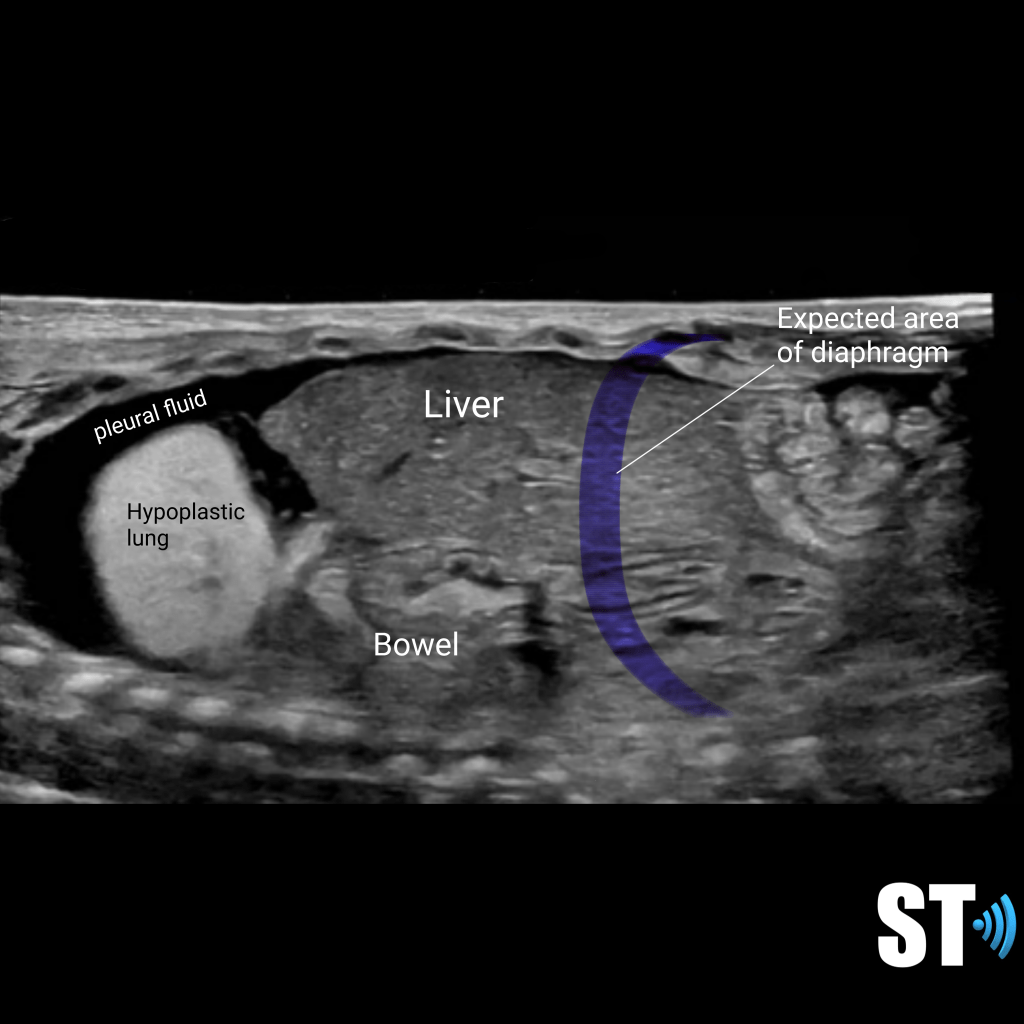

Diaphragmatic Hernia

Congenital diaphragmatic hernia is a defect or hole in the diaphragm that allows abdominal contents to enter the chest cavity. Most cases are diagnosed prenatally. Neonates typically present with respiratory distress acutely after birth. The lung on the affected side is usually hypoplastic.

Right sided hernia with liver and hypoplastic lung

Diaphragmatic hernia with bowel